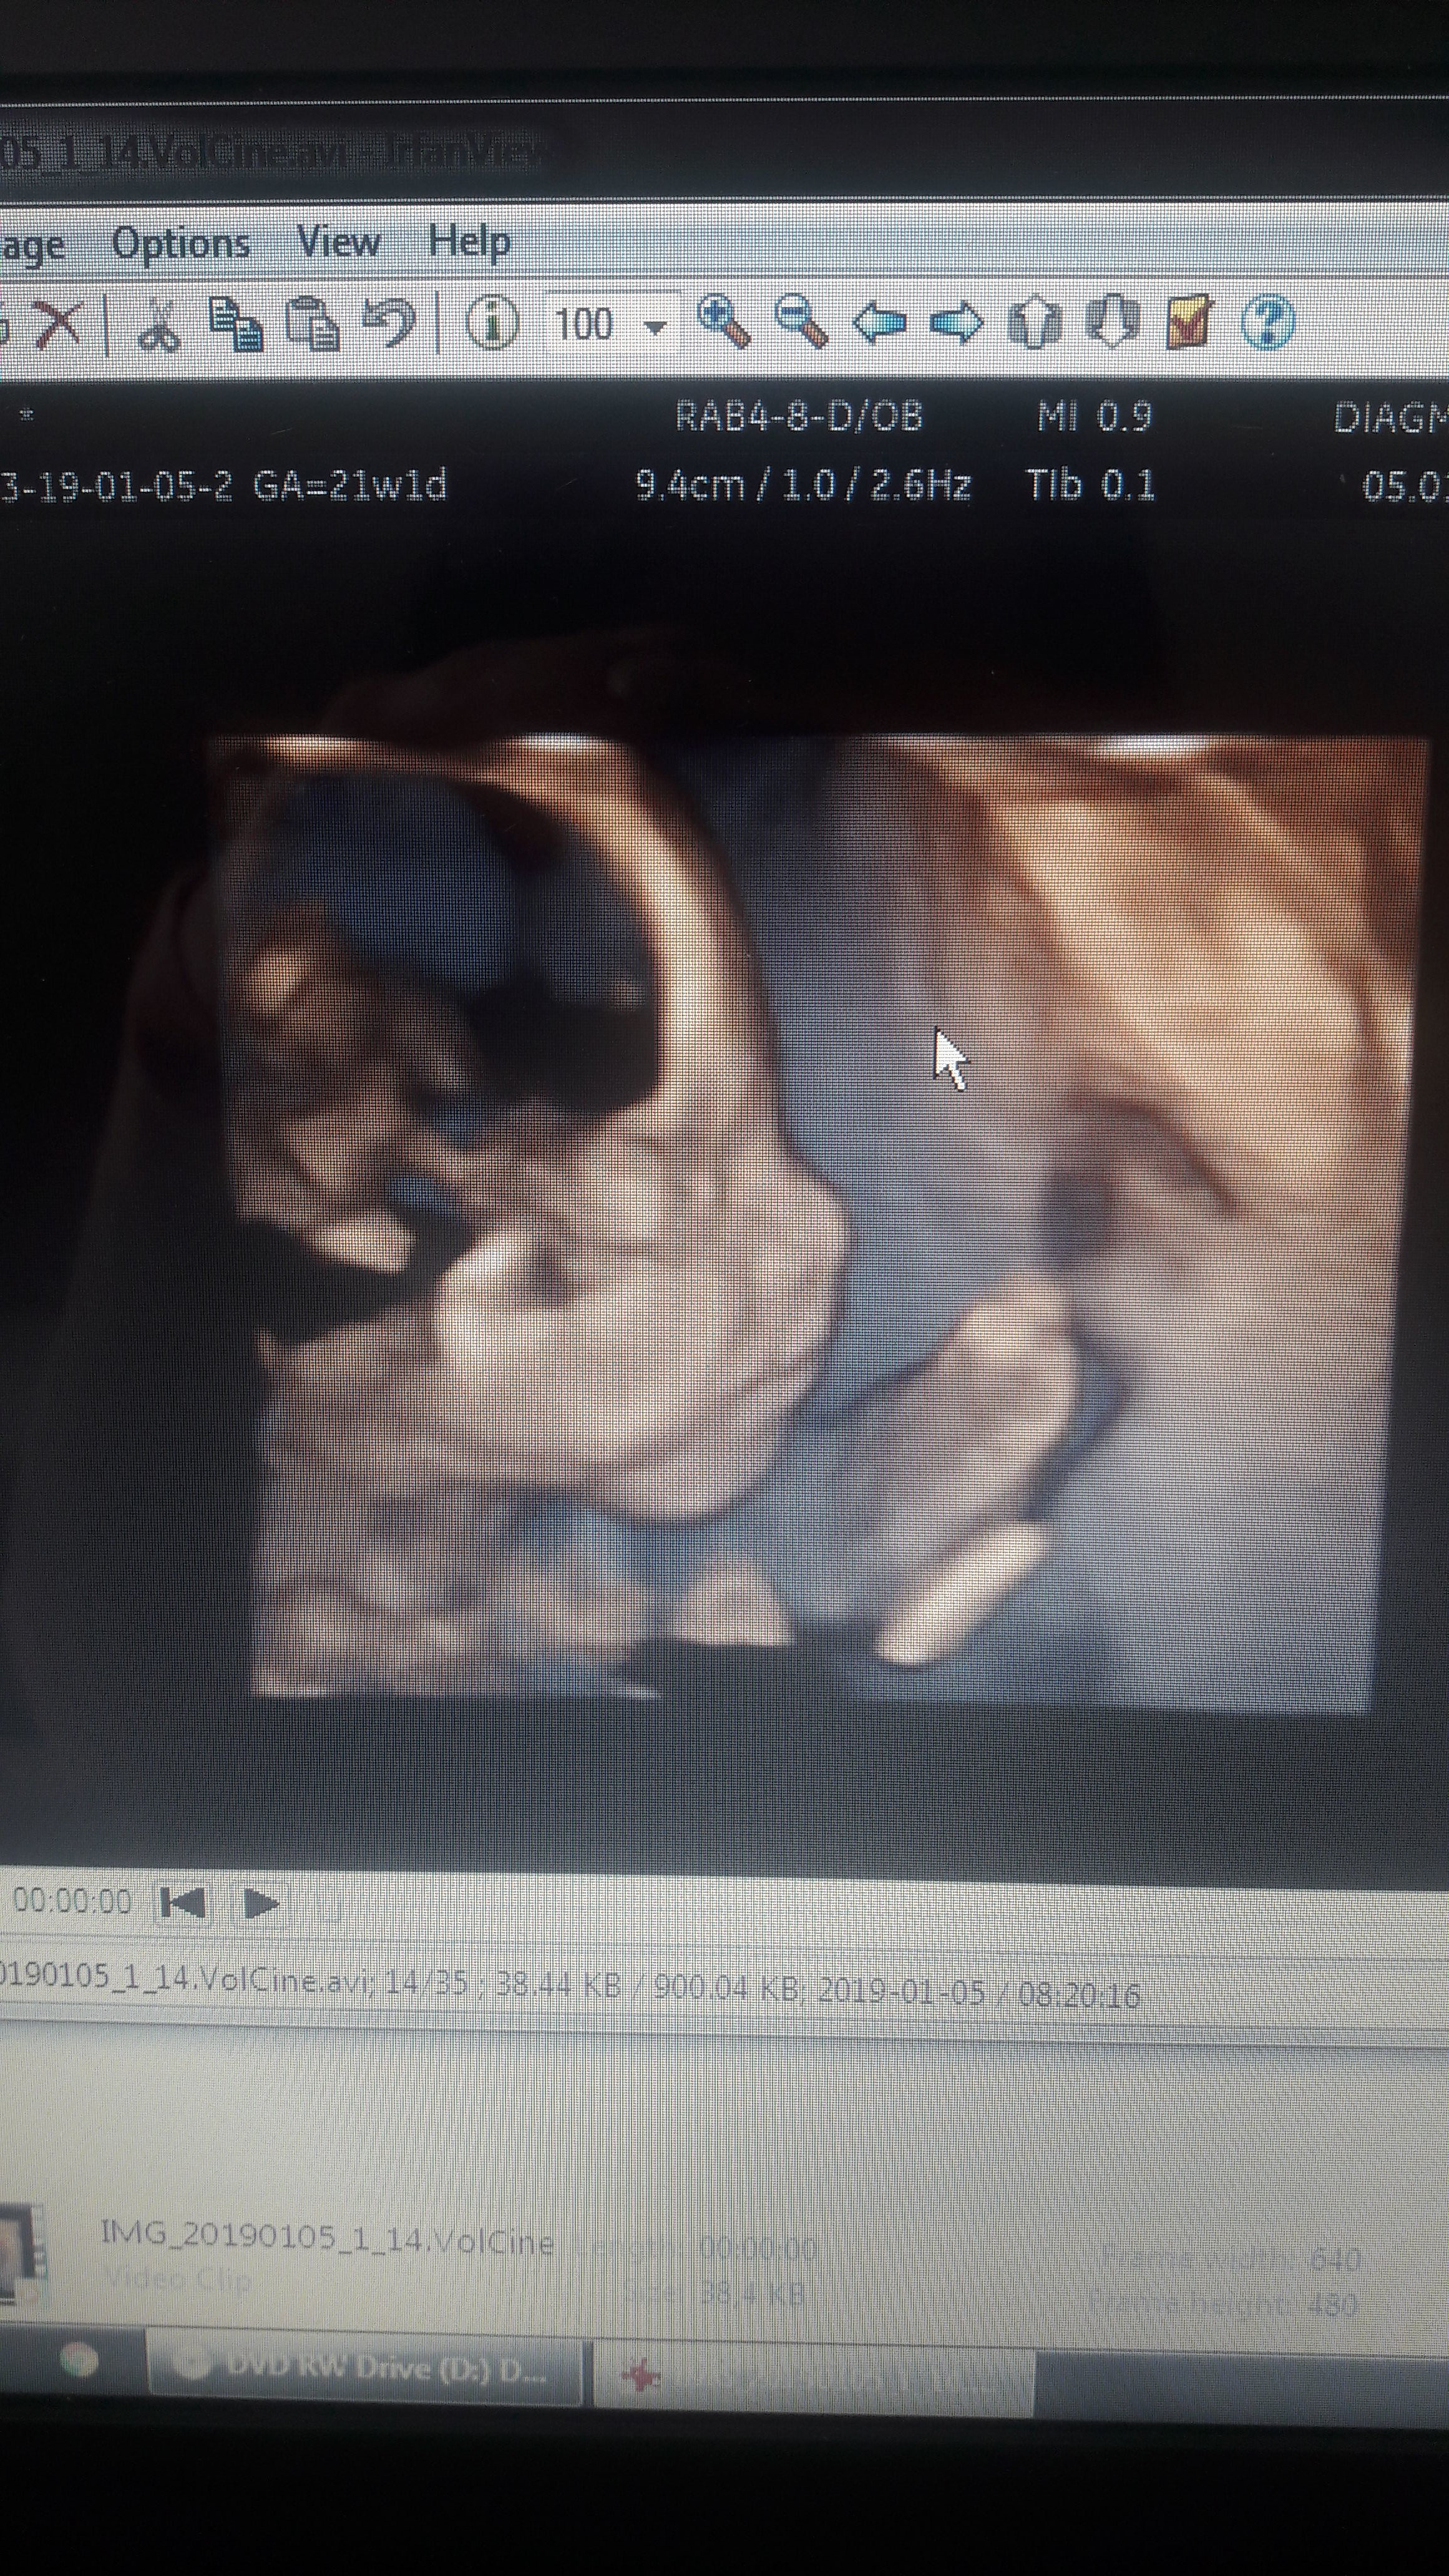

Majóweczki 2019

Hej dziewczyny ja po połówkowym. Wszystko w porzadku..dzidzia zdrowa:)) Nie chciala na poczatku buzi pokazać bo zasłaniała rączkami:) ale w końcu się udalo:) za to bez problemu pupką zaświeciła;p

IMG-20190105-WA0005.jpeg